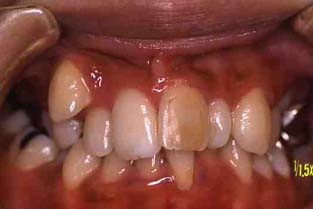

成人その3:八重歯と顎が狭い(唇側低位咬合,歯列狭窄) 22才,女性

矯正前

正面